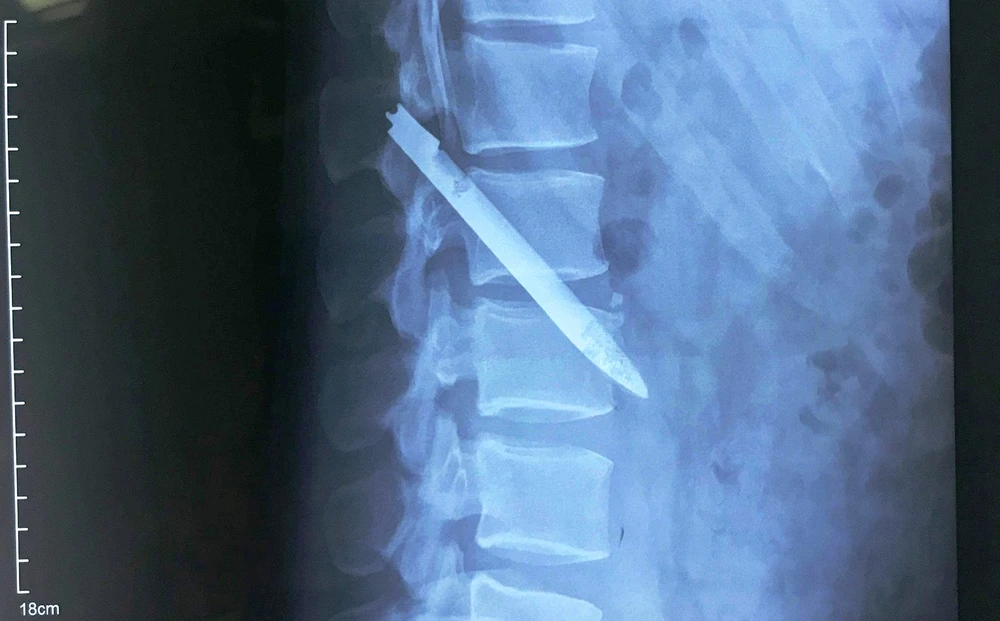

Lưỡi dao găm nằm trong người anh Nam suốt 11 năm qua. Ảnh: Hoàng Yến

Qua thăm khám và hình ảnh chụp phim X-quang, các bác sĩ và bệnh nhân vô cùng ngỡ ngàng, ngạc nhiên khi phát hiện hình ảnh dị vật kim khí dài, mỏng nằm chéo vùng cột sống thắt lưng.

Lưỡi dao nằm ở vị trí nguy hiểm, sát động mạch chủ bụng, nếu bệnh nhân vận động mạnh có thể khiến lưỡi dao di chuyển gây tổn thương mạch máu, ảnh hưởng đến tính mạng.

Đến ngày 17-4, các BS khoa Phẫu thuật Thần kinh cột sống, BV Hữu nghị Đa khoa Nghệ An đã thực hiện ca phẫu thuật lấy ra lưỡi dao găm nằm chéo vùng cột sống thắt lưng của anh Nam. Lưỡi dao dài 13 cm, đã hoen gỉ.